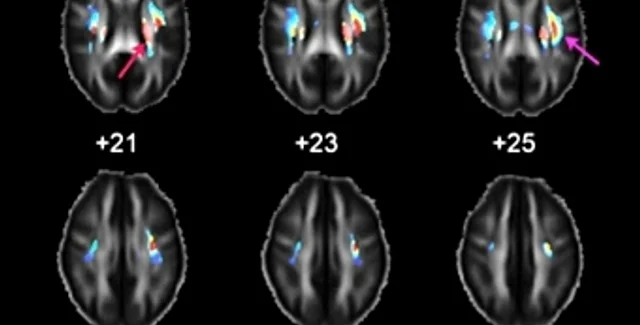

В исследовании участвовало 472 добровольца из Австралии, в числе которых были 85 пар генетически идентичных (однояйцевых) близнецов, 100 пар неидентичных близнецов, их родные братья и сестры. В ходе эксперимента добровольцы выполняли тесты IQ и проходили магнитно-резонансную томографию.

Ученые обращали внимание на объем отдельных структур мозга и особенности проведения нервных импульсов нейронами. Исследователи измеряли электрическую изоляцию индивидуальных нервных волокон - чем она выше, тем быстрее нейроны проводят сигналы. Полученные результаты сопоставлялись с генетическими данными добровольцев.

Авторам удалось найти 24 варианта шести генов, обладание которыми было связано с лучшей электрической проводимостью в мозге. Эти варианты представляли собой однонуклеотидные полиморфизмы (SNP) - изменения в последовательности гена размером в один нуклеотид. Помимо лучшей электрической проводимости, некоторые из обнаруженных полиморфизмов также были связаны с повышенными на несколько пунктов результатами тестов IQ.